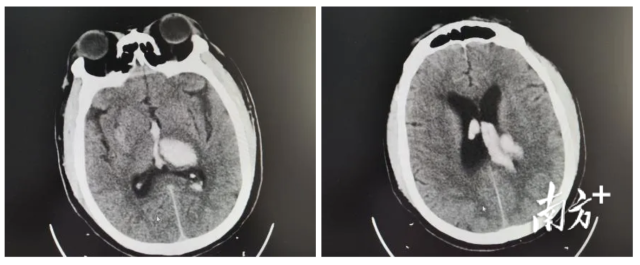

独居男子突发脑出血,高明医生与死神“抢人”